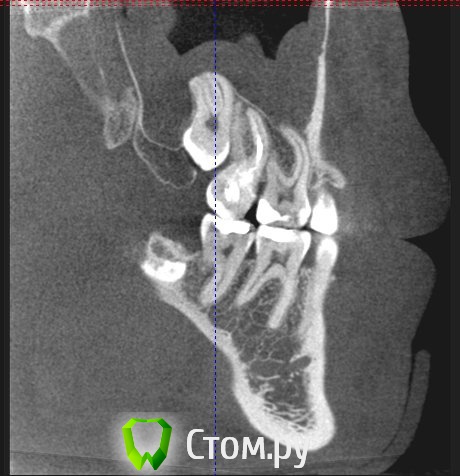

Сергей_vrn36 Опубликовано 3 марта, 2014 Поделиться Опубликовано 3 марта, 2014 (изменено) пару недель периодически ноет в районе 7-8 зубов (ну которые верхние, справа). плюс ко всему, когда ноют зубы закладывает нос. 8й зуб мудрости лезет уже второй год и думаю уже и не вылезет - на снимке видно, что он упирается в низ 7-го, находясь как бы между корнями (ну это я так снимки рассмотрел). в клиниках врачи говорят, что такие зубы удаляют в стационарах, т.к. он выходит почти наполовину в носовую пазуху. какие вобще прогнозы по поводу удаления этого зуба, чего мне следует начинать бояться? - корень там завитком, заходит в пазуху и мне кажется будет цепляться за дно при удалении. какова вероятность, что он (корень) останется в пазухе при удалении зуба и какая будет нужна операция(?), чтобы потом его оттуда достать?ps/ наверно надо было в другом разделе темку сделать. но я рад любому совету. Изменено 3 марта, 2014 пользователем Сергей_vrn36 Ссылка на комментарий